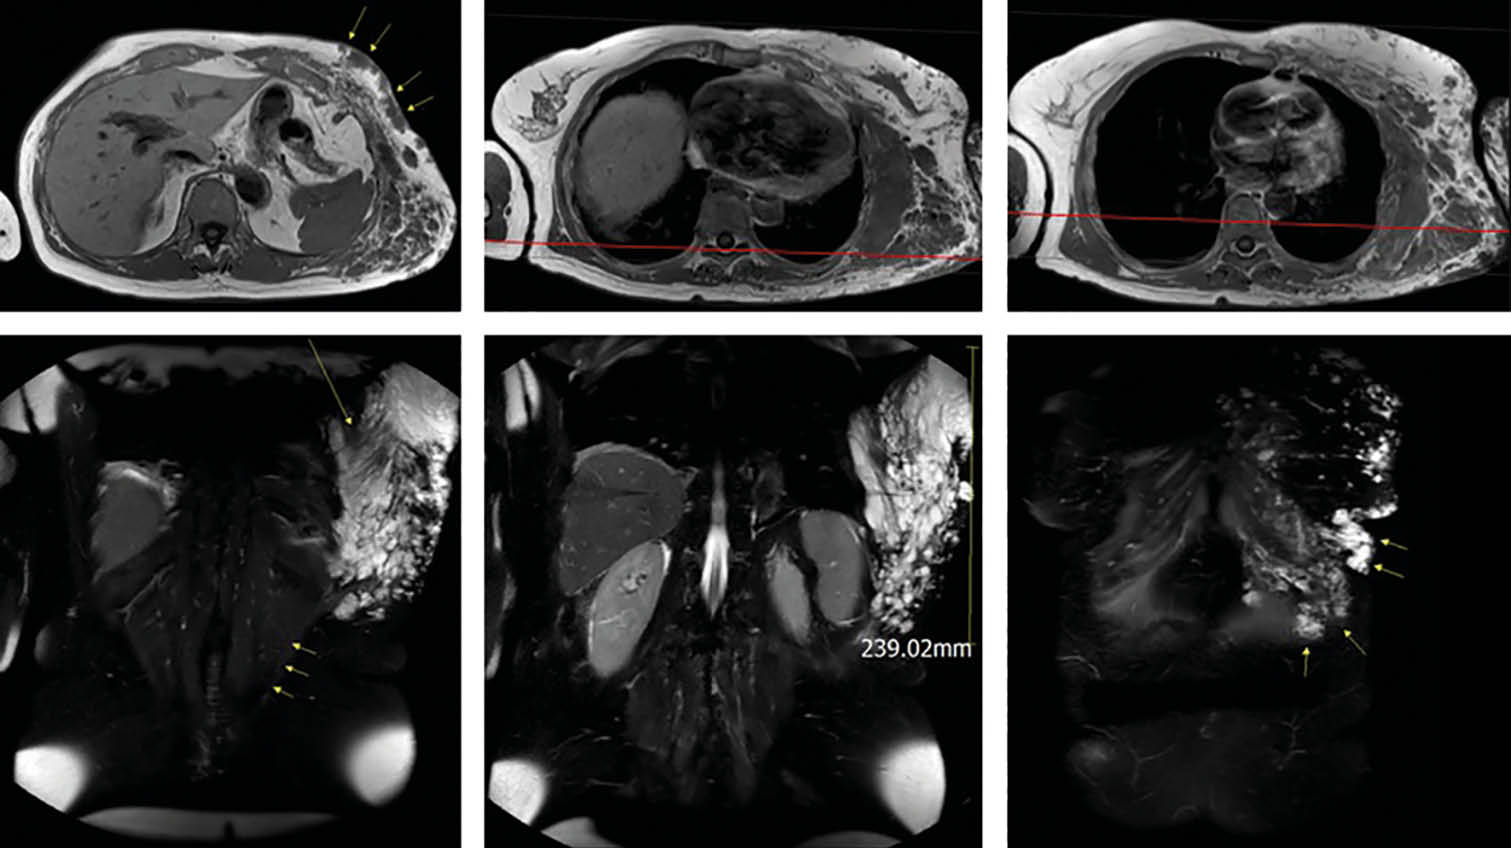

Aufgrund der symptomatischen Cholezystolithiasis nach stattgehabter akuter Cholezystitis wurde die Indikation zur elektiven laparoskopischen Cholezystektomie gestellt. An diagnostischen Verfahren wurden auswärts ein Angio-MRT (Abb. 1 – 4) des Oberbauches und eine Magnetresonanz-Cholangiopankreatikographie (MRCP) durchgeführt, welche eine Cholezystitis bei Cholezystolithiasis und eine beginnende Leberzirrhose nachweisen konnten. Im Rahmen der präoperativen Vorbereitung wurde eine Echokardiographie durchgeführt, in welchem eine Herzinsuffizienz infolge der Volumenbelastung durch die AV-Shunts i.R. des KMS und eine „Cirrhose cardiaque“ ausgeschlossen werden konnten. Als Marker einer intravasalen Gerinnungsaktivierung wurden erhöhte Prothrombinfragmente, D-Dimere und eine erniedrigte Antiplasmin-Konzentration sowie eine gesteigerte Fibrinolysekapazität detektiert. Eine sekundäre Thrombozytopenie oder eine Fibrinogen- und Faktor-XIII-Verminderung konnten ebenso wie das Vorliegen eines erworbenen von-Willebrand-Syndroms ausgeschlossen werden.

In einer hämostaseologischen Vorstellung wurde die Pausierung der Thrombozytenaggregationshemmung über 7 d unter „Bridging“ mittels niedermolekularem Heparin und eine medikamentöse Hemmung der Hyperfibrinolyse durch Tranexamsäure bis zum 3. postoperativen Tag bzw. in Abhängigkeit von Klinik und des hämostaseologischen perioperativen Monitorings empfohlen. Als perioperative Antibiotikaprophylaxe wurde Imipenem eingesetzt. Der Kameratrokar wurde entsprechend der aus dem Angio-MRT bekannten linksseitigen Ausprägung der Gefäßmalformationen (Abb. 1 – 4) in typischer Nabelposition platziert.

Abb. 3: KM-verstärkte fettunterdrückte axiale T1-Sequenz:

Tubulär-granuläre KM-anreichende Befunde mit Beteiligung der Interkostalmuskulatur (rote Pfeile), der Oberarmmuskulatur (blaue Pfeile) und der Kutis (weiße Pfeile). Auffällige Begrenzung der Malformation auf einen Quadranten des Körperstammes

(siehe weiße Mittellinie)